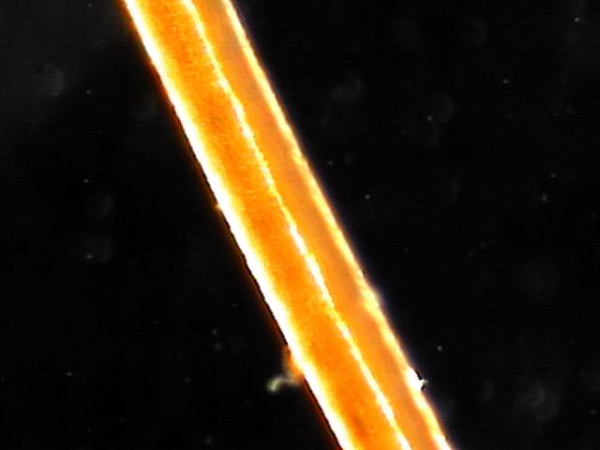

전립선과 사정관과 정낭 그리고 정관등이 표적치료를 한다음 배출된 정낭의 결석과 혈정액의 현미경 학적 검사 자료상 머리카락의 굵기와 비교하여 치료를 하므로 열심히 치료하여 건강하게 삶을 삽시다.

This is a microscopic examination of seminal vesicle stones and hematospermia discharged after targeted treatment of the prostate, ejaculatory ducts, seminal vesicles, and vas deferens. By comparing their size to the thickness of a human hair, we can see the importance of precise treatment. Let’s continue treatment diligently and live a healthy life.